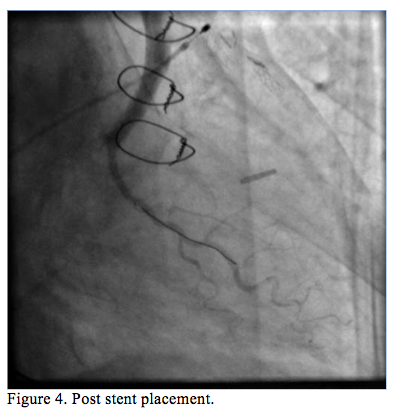

Improved flow (TIMI grade 2) was immediately seen, and a discrete lesion was apparent just proximal to the anastomosis of the SVG graft to OM1 artery (Figure 3). A VeriFLEX OTW bare-metal stent was deployed. After postdilatation and injection of 180 mcg intracoronary adenosine, there was TIMI grade 3 flow at the SVG to OM1 (Figure 4, Video 3), ST elevations nearly resolved, and the patient expressed immediate relief of chest pain. Intravenous abciximab was infused (10 mcg/min) for 12 hours postprocedure. Echocardiography the following day revealed severely decreased left ventricular systolic function (ejection fraction <25%) with akinetic inferior, posterior, and anterolateral walls.